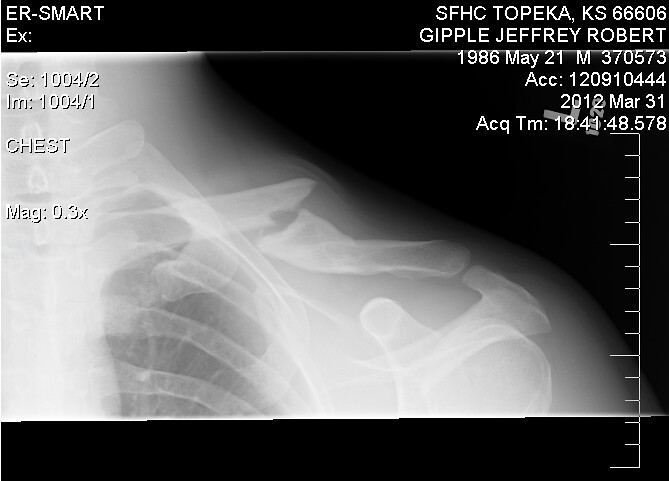

Badly broken collar bone. FROM A PASS ON A WARMUP LAP!

Its my second break, you can see where the lump was from the first one. Its surgery this time for sure, I cant have an 'M' shaped clavical!!!

Blade, mines going to go a little less smoothly because they are going to have to bend the plate around where it healed 3 years ago... Doctor is just worried about me breaking it again and having a shoulder full of loose screws.